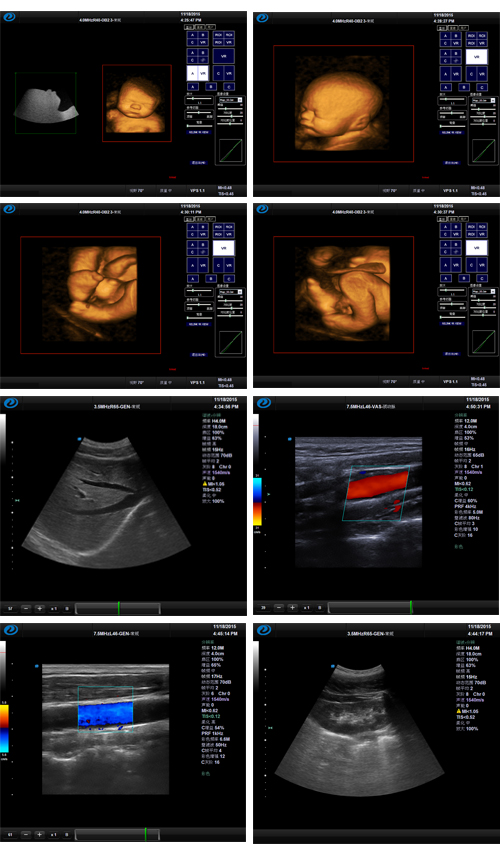

臻影(專家版) 全數字彩色多普勒超聲診斷儀

臻影(專家版),全數字彩色多普勒超聲診斷儀,推車式彩超

臻影(專家版)是基于高速PC平臺的全身應用型彩色多普勒超聲波診斷系統。

結合全新的技術平臺,保證最佳圖像性能的完美呈現。

優質的四維成像技術:

四維圖像實時顯示

通過立體光源成像,還原胎兒真實容貌

景深成像,增加立體感

重建(3D)和實時三維成像(4D)